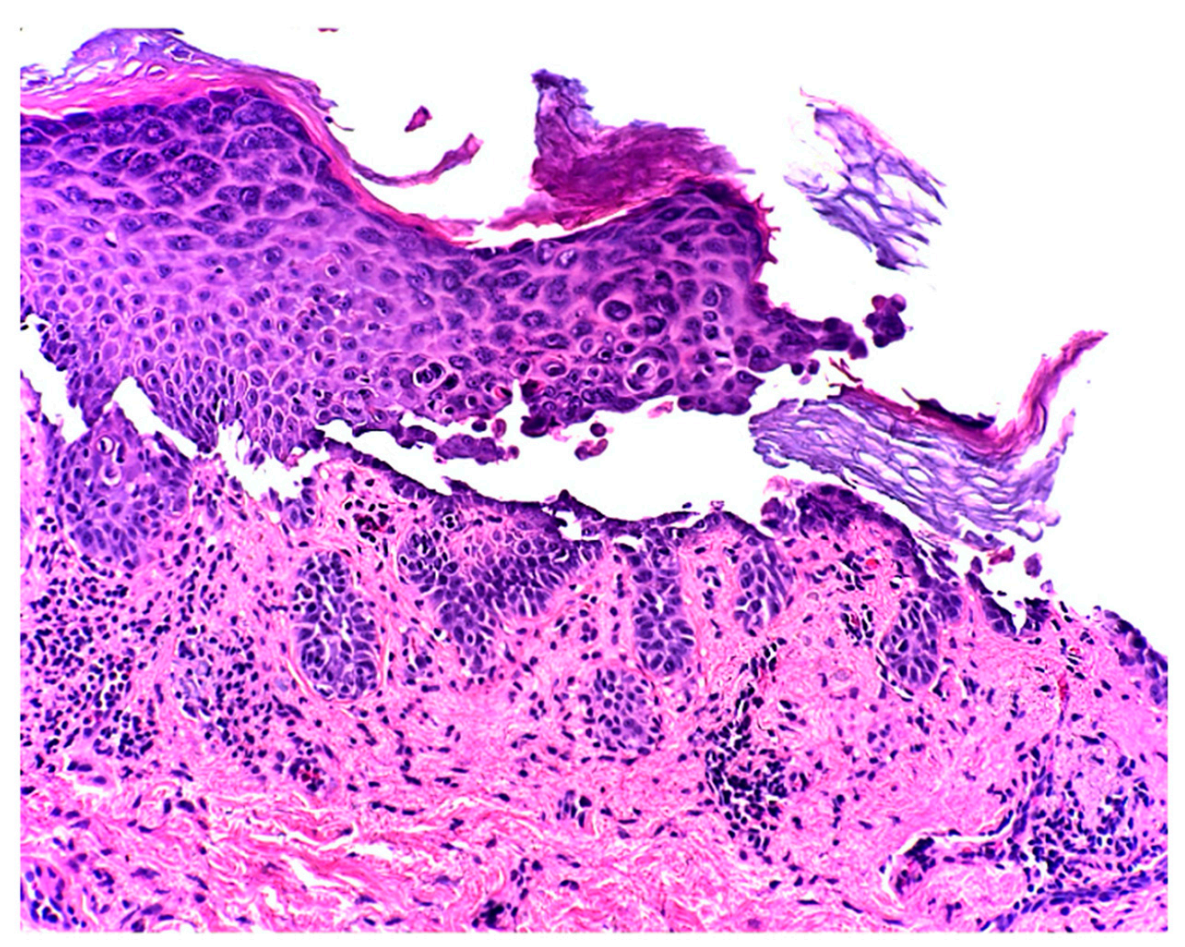

A Rare Case of Transient Acantholytic Dermatosis (AKA. Grover’s Disease) with Concomitant Pediculosis Pubis: An Atypical Presentation and First Documented Case Report

- Lacarrubba, F.; Boscaglia, S.; Nasca, M.R.; Caltabiano, R.; Micali, G. Grover’s disease: Dermoscopy, reflectance confocal microscopy and histopathological correlation. Dermatol. Pract. Concept. 2017, 7, 51–54. [Google Scholar] [CrossRef] [PubMed]